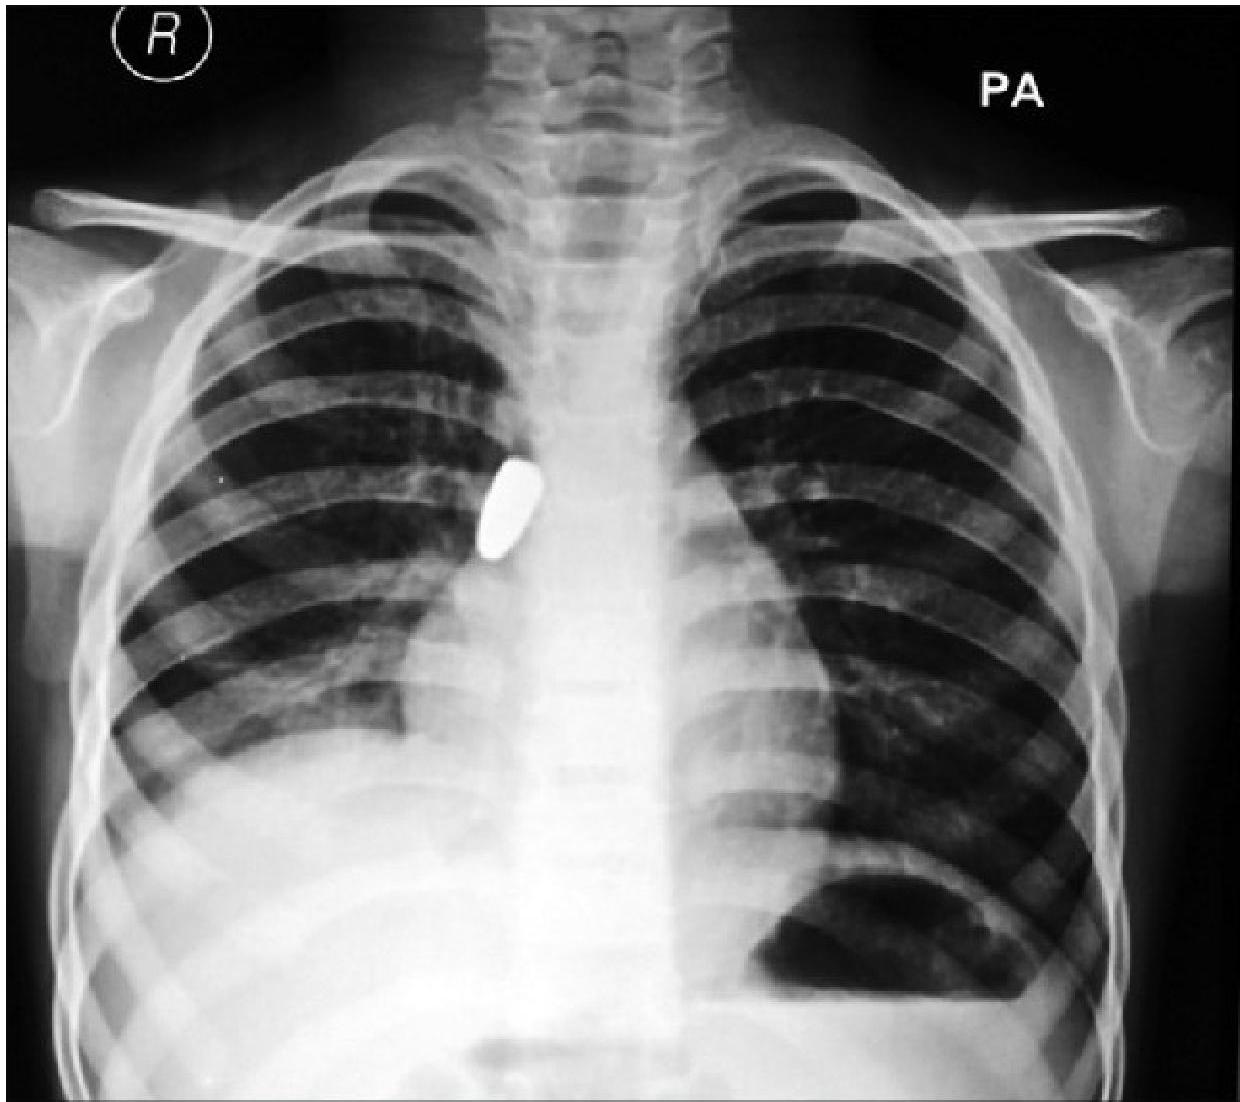

- 10% of FBs are radiopaque.

- Bronchial FBA Findings in chest x-ray:

- Hyperinflated lung

- Atelectasis

- Mediastinal shift

- Pneumonia

Left: Focal pneumonia in lower right lung lobe due to aspiration and airway obstruction. Right: Coin in the esophagus.